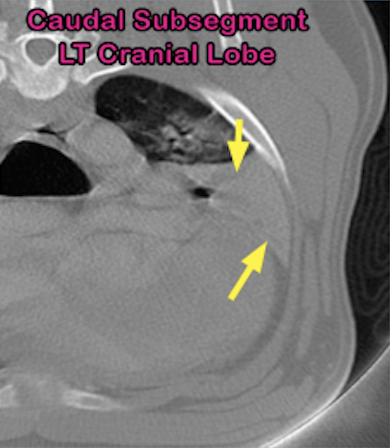

6-year-old American Bulldog with left-sided, muffled lung sounds received thorax CT scan to determine the cause.